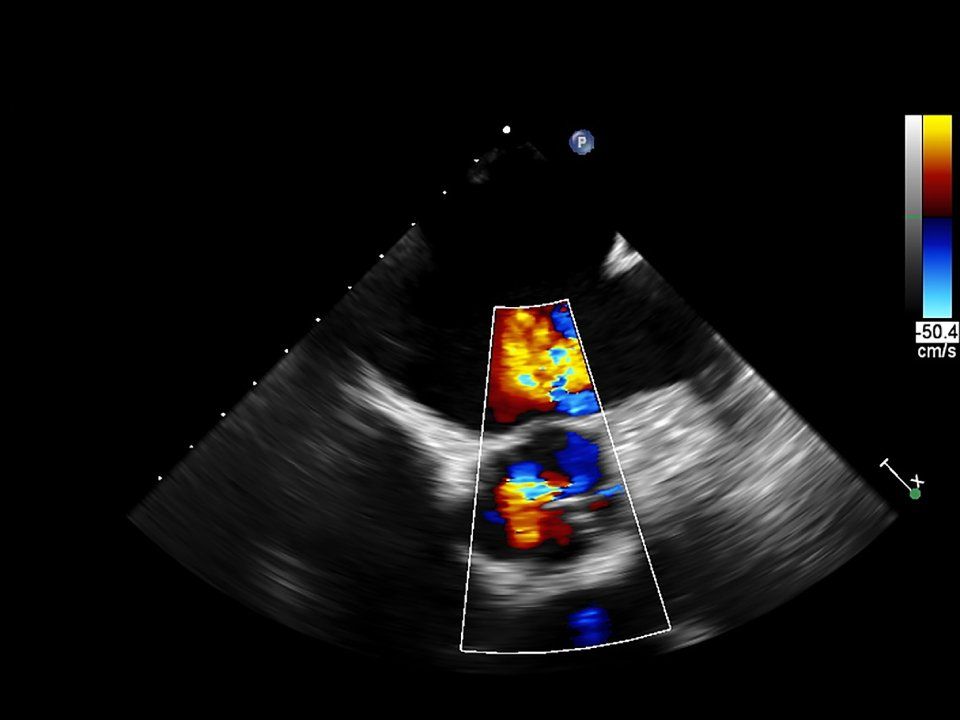

L'ecocolordoppler è un esame non invasivo e indolore, tramite il quale si possono visualizzare i principali vasi sanguigni e il relativo flusso ematico al loro interno.

Questo tipo di esame viene utilizzato in particolare nella valutazione di stenosi vascolari, soprattutto carotidee o delle arterie degli arti inferiori, nella diagnostica delle patologie venose, come ad esempio l'insufficienza venosa o la trombosi.